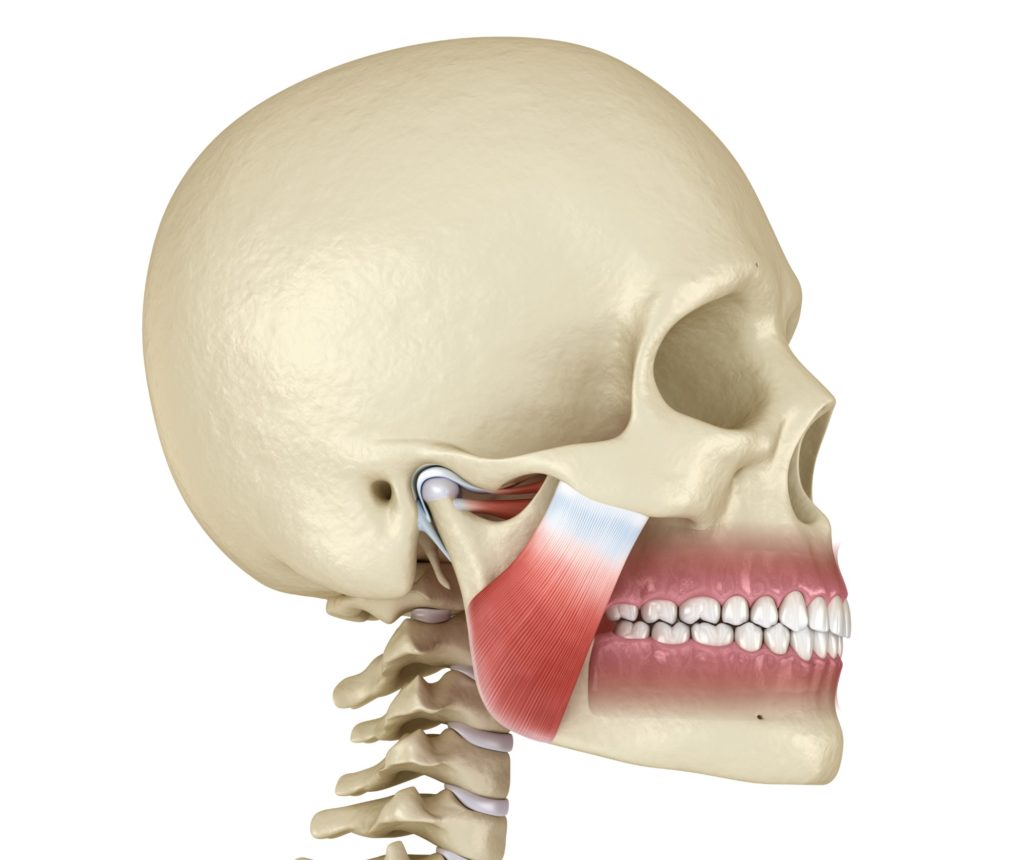

اضطرابات المفصل الصدغي الفكي والتھاب المفصل الصدغي الفكي: یسمى المفصل عند تقاطع العظام

یوجد مفصلان على جانبي الجمجمة أمام .(TMJ) الصدغیة مع الفك السفلي المفصل الصدغي الفكي

الأذنین. المفاصل متحركة وتعمل معا لتوفیر حركات فك سلسة. ومع ذلك ، في بعض الأحیان تتحول

العضلات المرتبطة بالمفصل ، مما قد یؤدي إلى العدید من المشاكل. یمكن أن یحدث اضطراب المفصل

The joint at the junction of the temporal bones with the lower jaw is called the temporomandibular joint (TMJ). Two joints are on both sides of the skull in front of the ears. The joints are mobile and work together to provide smooth jaw movements. However, sometimes the muscles attached to the joint shift, which can lead to many problems. TMJ disorder can be caused by many factors, such as dental, myogenic, joint, or anatomical factors. To diagnose, the doctor will check your jaw joints for pain or tenderness and listen for clicks when you move them. He will also see that the jaw works properly and doesn’t lock when opening or closing your mouth. He will also check for problems with your facial muscles. The doctor may take a full X-Ray to evaluate your jaw and teeth. Other tests like magnetic resonance imaging (MRI) or computer tomography are also conducted. The MRI can show if the TMJ is in the correct position.